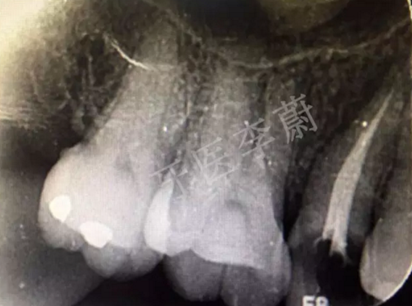

15牙根管充填術(shù)后X牙片

15牙根管預(yù)備試尖片